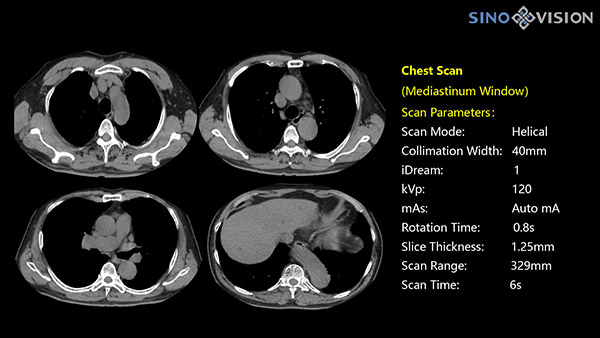

Инновационный 128-срезовый компьютерный томограф SinoVision InsitumCT 568 – это сочетание высокой скорости работы, низкой дозы и максимума возможностей для подавляющего большинства клинических случаев, как в рутинных, так и в углубленных специализированных исследованиях, в том числе педиатрические и кардиологические исследования при сверхнизких дозах.

Полнофункциональный 128-резовый компьютерный томограф InsitumCT 568 - это лучшее в новом поколении широкодиапазонных томографов с 128 срезами и большой диафрагмой. Этот КТ-сканер с большой апертурой обеспечивает 128 срезов КТ с диафрагмой 76 см, улучшает разрешение изображения до 21Lp/cm, помогает точно диагностировать и лечить заболевания, а также значительно улучшает клинические характеристики и расширяемость оборудования. Позволяет реализовать визуализацию в высоком разрешении и в малых дозах лучевой нагрузки.

Полнофункциональная платформа клинической диагностики может точно определять местонахождение и диагностировать общие повреждения качественно и количественно, а также достигать полнофункциональных клинических показателей, включая обширные кардиологические исследования со сверхнизкими дозами лучевой нагрузки.